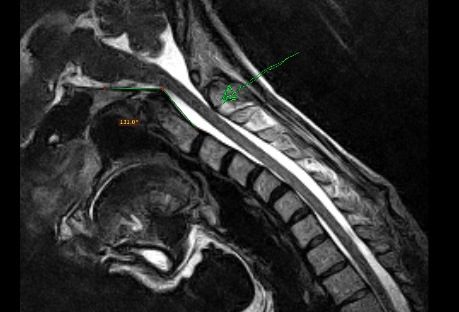

Cranio-cervical instability means *inappropriate positioning AND/OR movement of the cervical vertebrae* (including fracture), thus compromising spinal cord, and potentially also the nerves that come out of it

Our breathing impulse can be affected by any injury occurring between the brainstem and C4-C5, and this can occur without affecting other nerves.